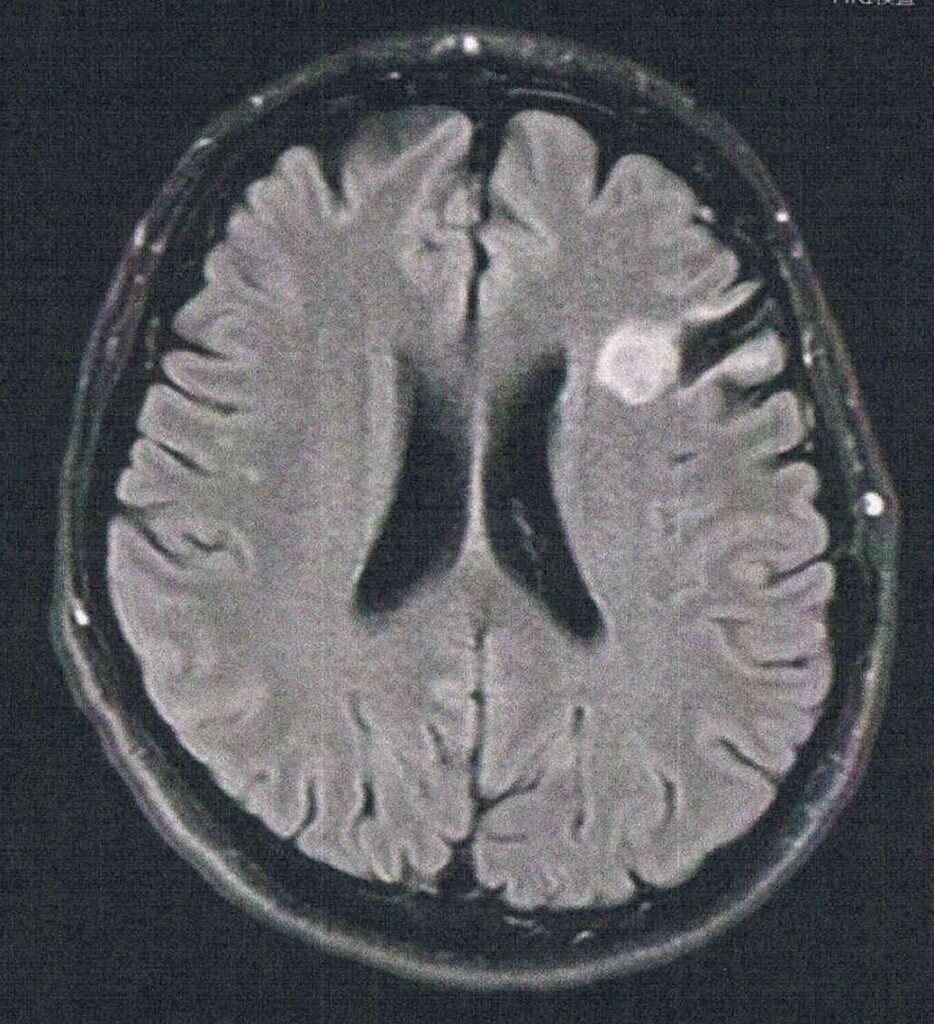

手術から8.5年が経過した。半年ごとの定期検査です。

- 悪性転化しやすい腫瘍の種類(びまん性星細胞腫グレード2)

- 造影剤を注射してMRI検査

- 1年前と比べて拡大は無し。造影剤でも問題なし。